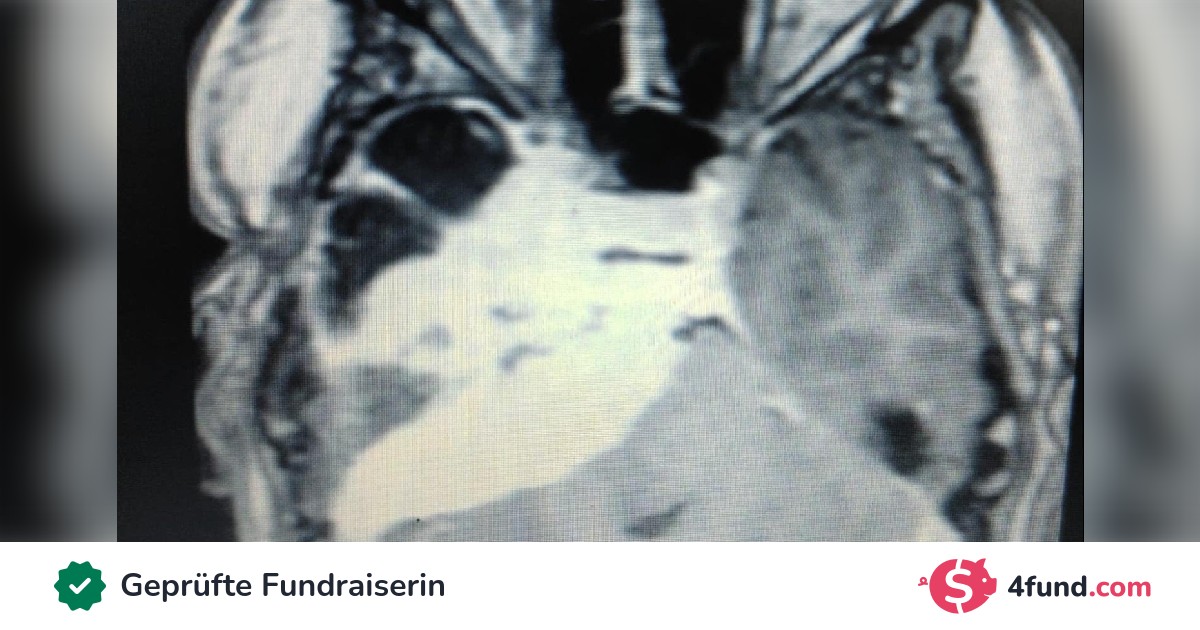

Mein Name ist András Tősér, und ich suche verzweifelt nach einer Lösung zur Finanzierung meiner Operation in Berlin. 2012 wurde bei mir ein Hirntumor (Tentorium Meningeoma) diagnostiziert. Ich habe mich in den letzten 12 Jahren mehreren chirurgischen Eingriffen unterzogen, aber das Tentorium Meningeom - aufgrund seiner Lage im Hirnstamm - wurde bei den Operationen nur teilweise entfernt. Derzeit ist der Tumor größer als 7,5 x 5,5 x 3,5 cm und verursacht erhebliche Schmerzen, Schwindel, Doppeltsehen und einen vollständigen Hörverlust auf der rechten Seite. Nachdem ich mich mit mehreren ungarischen Neurochirurgen über weitere Therapiemöglichkeiten beraten hatte, wurde mir empfohlen, den Neurochirurgen Professor Dr. Peter Vajkoczy an der Charité in Berlin zu konsultieren. Ich setzte mich mit ihm in Verbindung, schickte ihm die angeforderten medizinischen Berichte, und er erklärte sich bereit, die Operation durchzuführen, aber die geschätzten Kosten von 71,4 Tausend Euro müssten aus irgendeiner Quelle finanziert werden. Nachdem ich den Kostenvoranschlag erhalten hatte, reichte ich einen Antrag bei der Nationalen Krankenkasse ein, der leider abgelehnt wurde. Im Moment habe ich keine andere Möglichkeit, als zu sammeln. Ich wäre für jede Unterstützung dankbar, die mir hilft, die Kosten für die Behandlung und die zusätzlichen Ausgaben zu finanzieren, damit ich wieder gesund werde und eine bessere Lebensqualität habe.